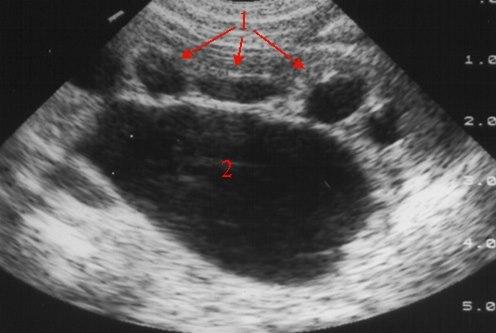

Overgangs-stenose (UL)

Kraftig utvidelse av calyces (1) og ekstrarenalt nyrebekken (2)